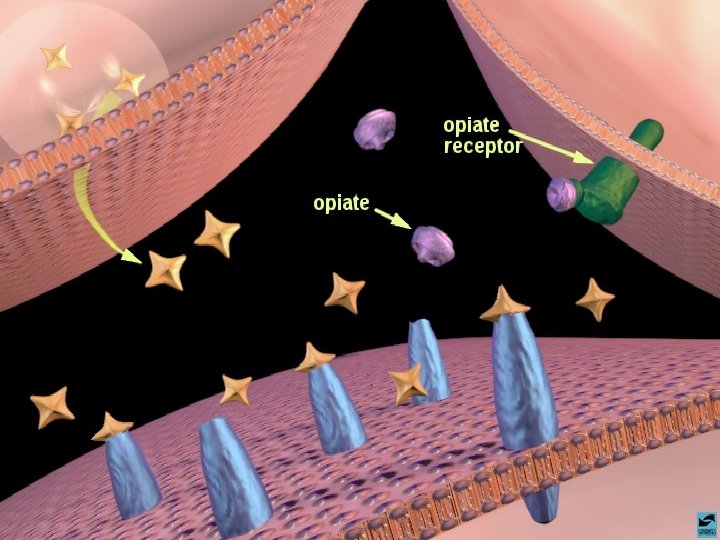

OS OPIÁCIOS EFEITOS CEREBRAIS OS OPIÁCIOS LIGAM-SE AOS RECEPTORES CEREBRAIS DE ENDORFINAS